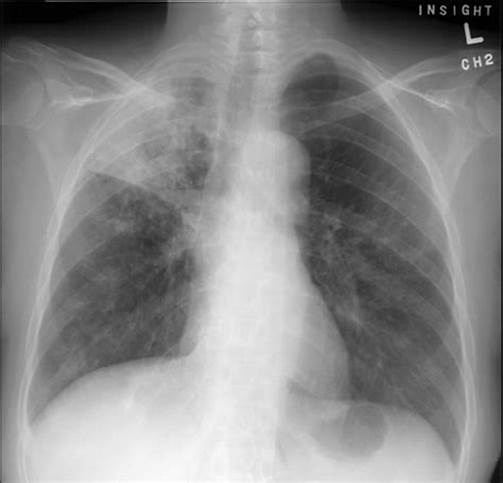

另外一个病例,男性,46岁,爱游泳,平时身体很棒,因发热、咳嗽就诊,肺部CT提示右上肺结核灶。

入院后,检查发现白细胞高,C反应蛋白高,痰多,呈黄色或灰色。

痰检阴性、T-SPOT阳性、PPD阴性。

医生的诊断是打了问号的肺结核和肺炎,正要抗结核治疗,患者也准备吃药。